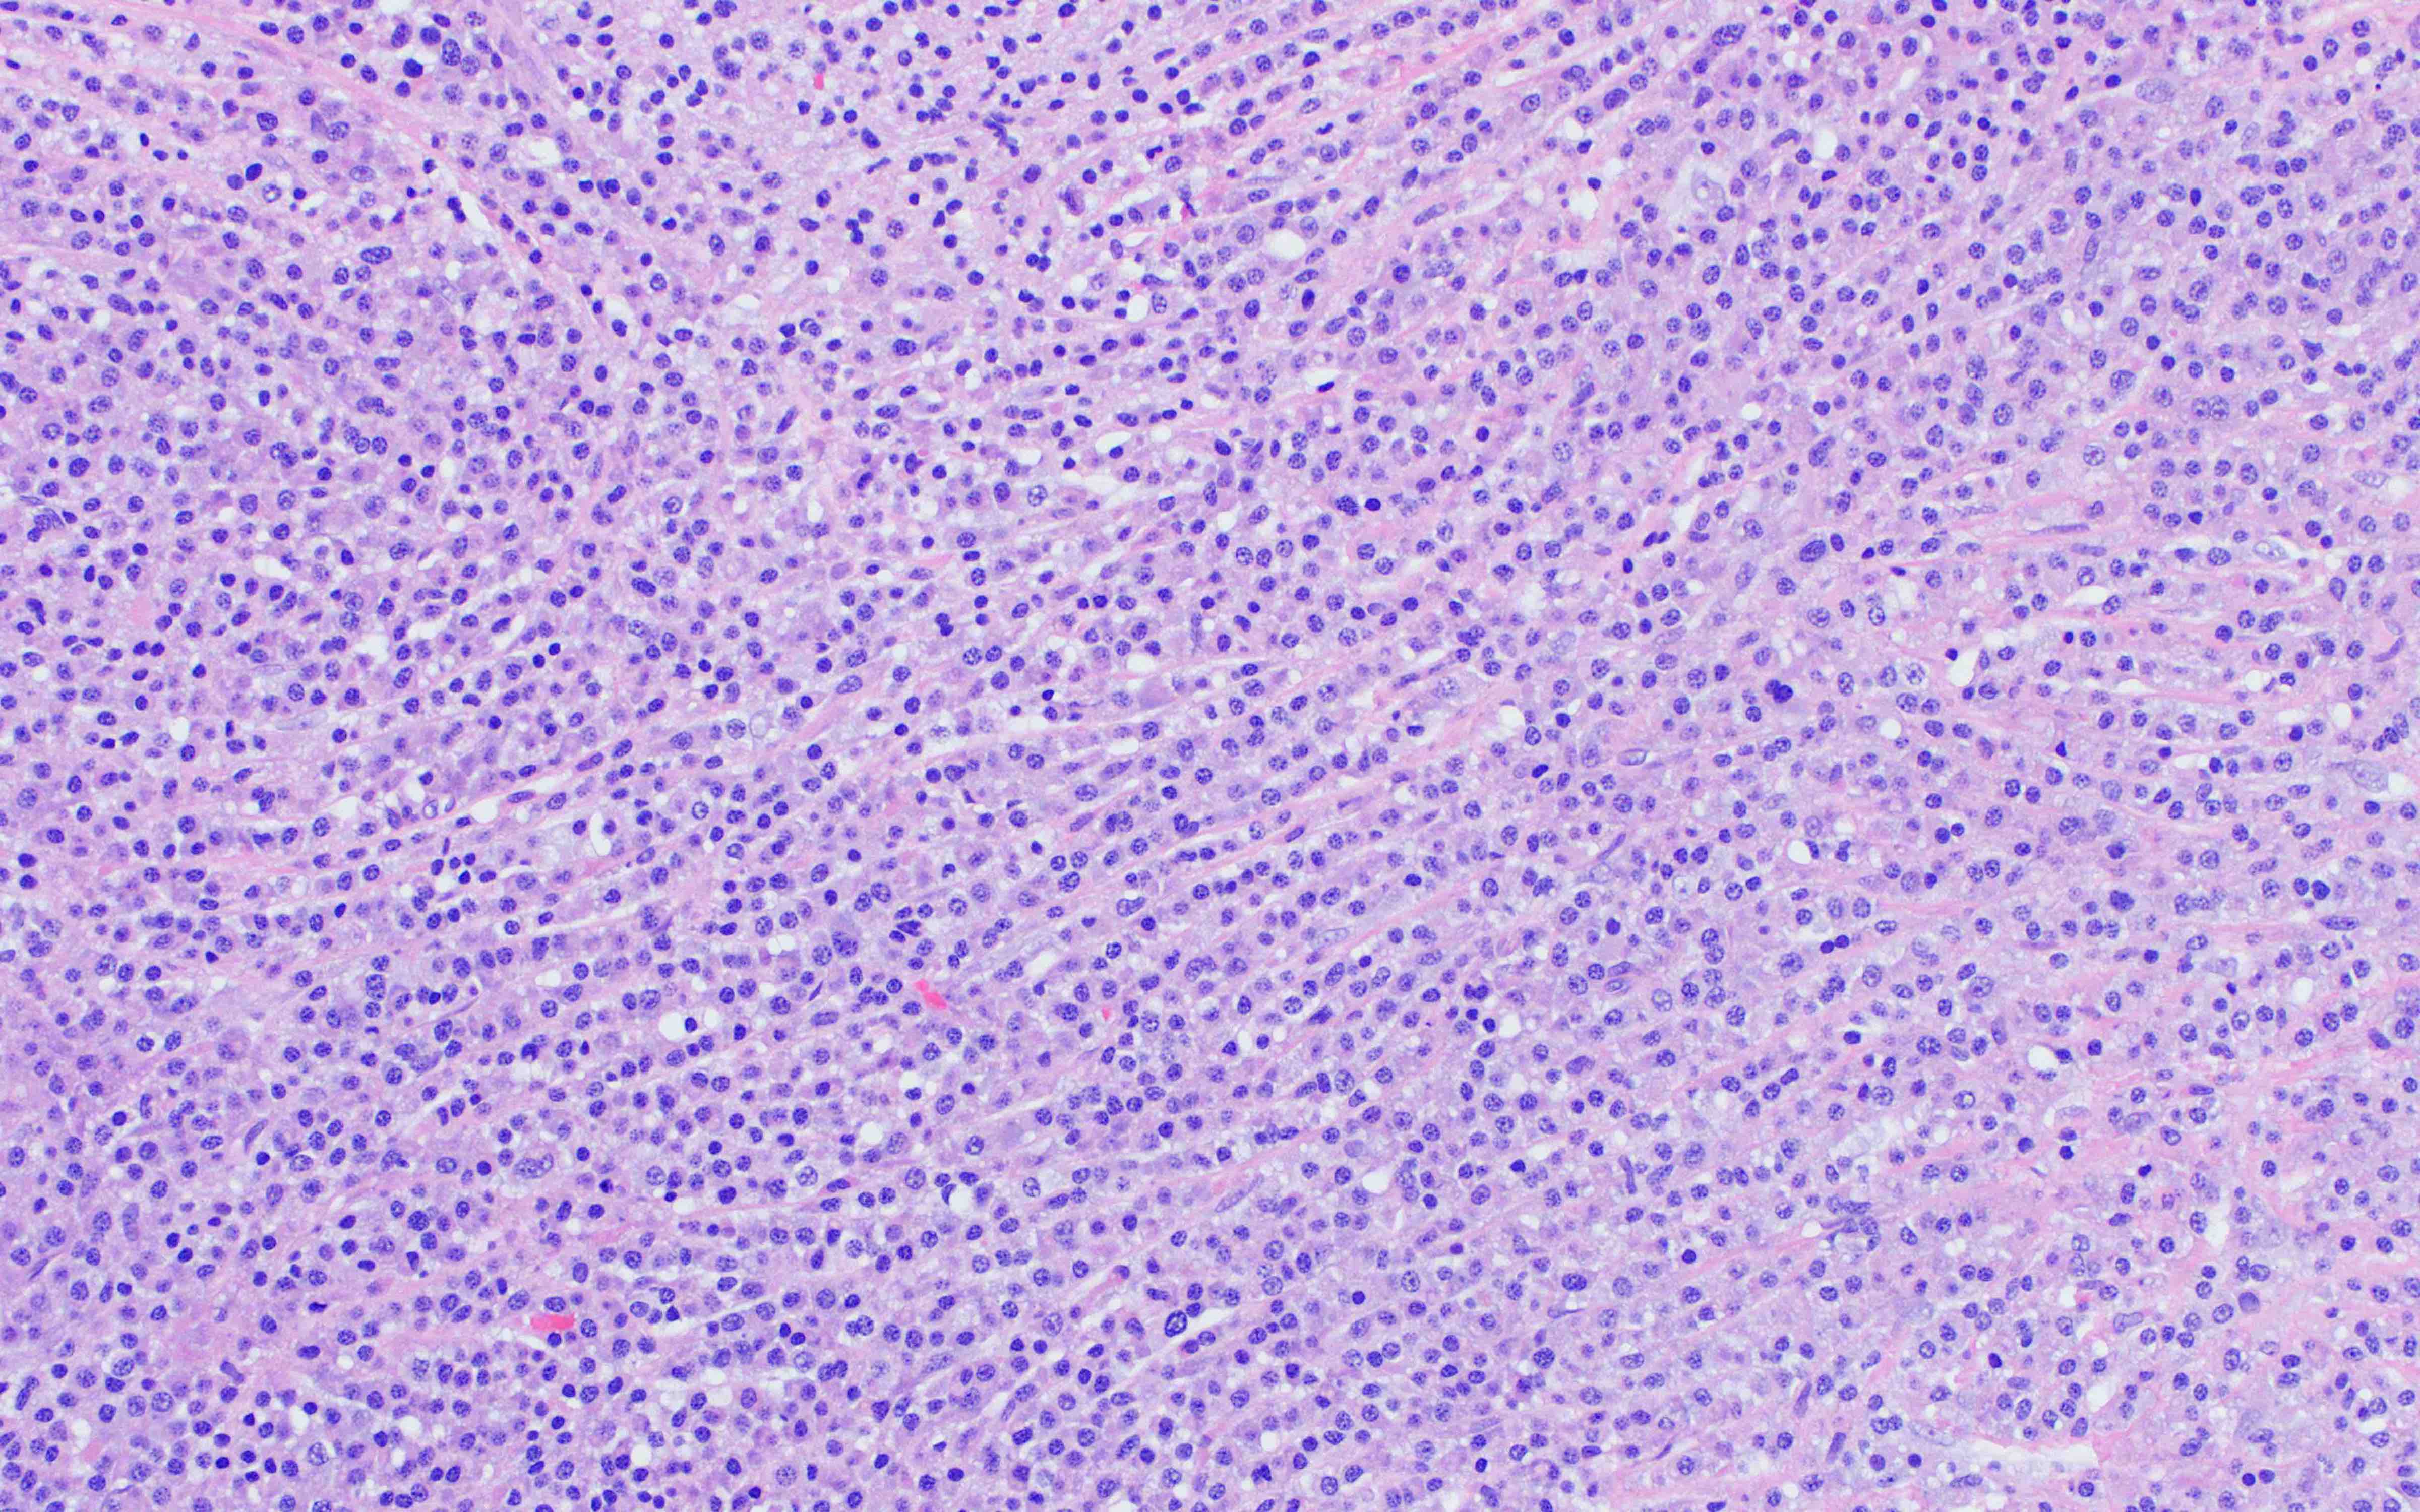

Microscopic (histologic) description

- Core biopsy (Am J Clin Path 1987;87:342):

- Interstitial clusters, nodules or sheets of plasma cells

- Areas of bone marrow may be spared with preserved hematopoiesis, other cases may have diffuse involvement and markedly suppressed hematopoiesis

- Prominent osteoclastic activity may be seen

- IHC to quantify plasma cells (CD138), stains for Ig kappa and lambda to establish clonality

Microscopic (histologic) images

Contributed by Genevieve M. Crane, M.D., Ph.D. and Tapan Bhavsar, M.D., Ph.D.